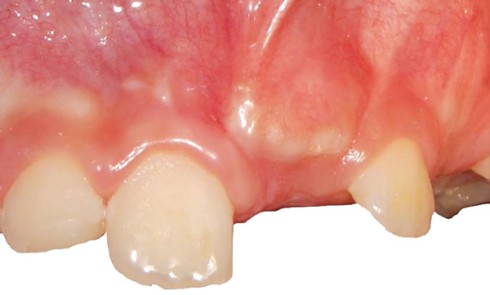

Article réservé à nos abonnés Le diagnostic muco-gingival en orthodontie : avant, pendant, après. Quand faut-il intervenir ?

L’un des objectifs de l’orthodontie est d’améliorer l’architecture dento-parodontale et par là même prévenir la survenue de pathologies parodontales sur...